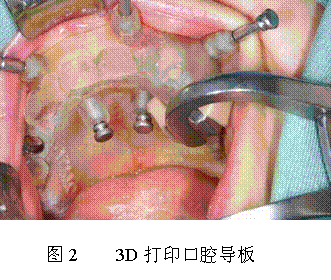

再如種植牙齒,目前種植一顆牙需要一兩萬塊,種植體本身就像一個螺絲一樣,怎么樣才能把假牙精確地種植在牙床上,在沒有用導板之前就完全要靠醫(yī)生的經驗,所以有的醫(yī)生高明收費也相對要高,這就是為什么種植一顆小小的牙需要花費那么高的原因,一顆假牙的重量就二三十克,價錢比黃金還要貴,實際上它的材料就是原始的不銹鋼、鈷鉻合金或鈦合金等。但如果有了導板的話(如圖2所示),種植牙的難度就會大大降低了,普通的醫(yī)生也能做到,這樣就能降低假牙種植的花費。